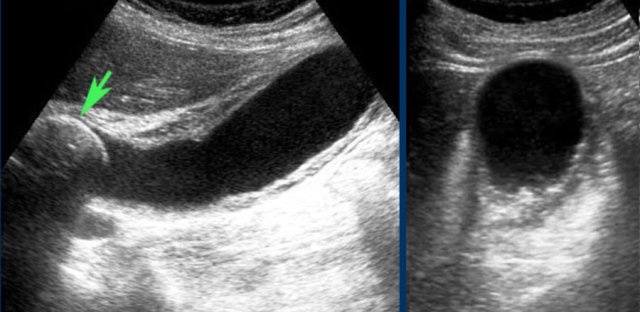

Even in the case, when there is intervening liver tissue between the abdominal wall and the gallbladder, an indirect “hydrops-sign” can be demonstrated.

The left image shows a gallbladder that keeps its rounded shape, without and during compression, and bulges into the soft interposing liver tissue and abdominal wall.

Likewise, the absence of hydrops can be demonstrated, even when there is intervening liver tissue, which is soft during compression (image on the right).